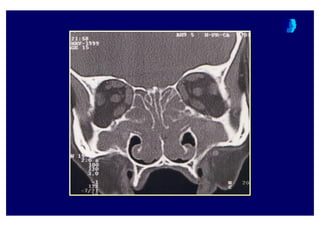

Water’s grafisiWaterWater’’ss grafisigrafisi

Coronal BTCoronalCoronal BTBT

BT ne zaman istenmelidir ?BT ne zaman istenmelidir ?BT ne zaman istenmelidir ?

• Yo4un bir tedaviye cevap al namad 4 taktirde

KBB uzman taraf ndan

• Komplikasyon riski ta( yan olgularda

• Pre-operative de4erlendirme